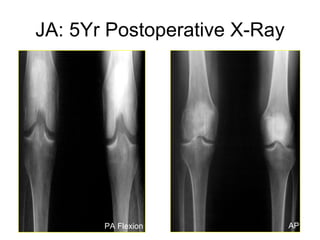

JA: 5Yr Postoperative X-Ray PA Flexion AP

JA: 5Yr Postoperative MRI Virtually unchanged meniscal allograft